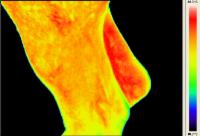

Rasmus - Pferd mit Arthrose - Horse with Osteoarthritis